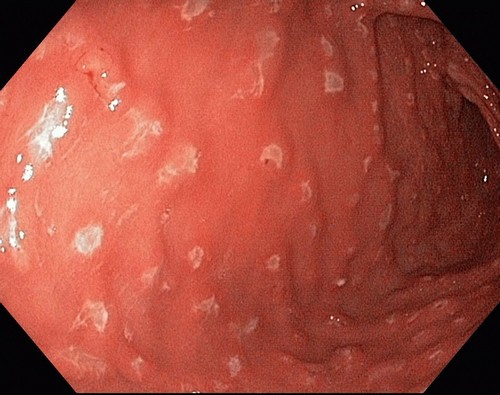

Гастрит принадлежит к воспалениям, поражающим слизистые оболочки желудка, способных вызывать дистрофические изменения в состоянии этого органа. Выражается это в виде нарушений, происходящих в регенерации эпителиальных клеток, в результате чего возникает их дистрофия с замещением на фиброзные ткани. Секреция желудка в этом случае нарушается с возможностью повышения выделения желудочного сока или гиперацидного гастрита. От содержания соляной кислоты в желудке зависят процессы переработки пищи, поступившей в желудок, а превышение ее способно привести к нарушениям функционирования всей желудочно-кишечной системы в организме человека. При такого рода патологии, особое внимание необходимо уделять питанию.

Гастрит, особенно сопровождаемый эрозивными воспалениям, нельзя вылечить без соблюдения специализированной диеты, которая в периоды обострения предусматривает строгое ограничение любой пищи, способной оказывать раздражающее действие на желудок. После купирования приступа также предусмотрена специальная диетотерапия, направленная на предупреждение усиленной выработки желудочного сока. В рационе таких больных обязательно должны присутствовать свежие фрукты и овощи, которые нужно предварительно отваривать и измельчать, а готовые блюда не должны содержать грубых и твердых частиц.